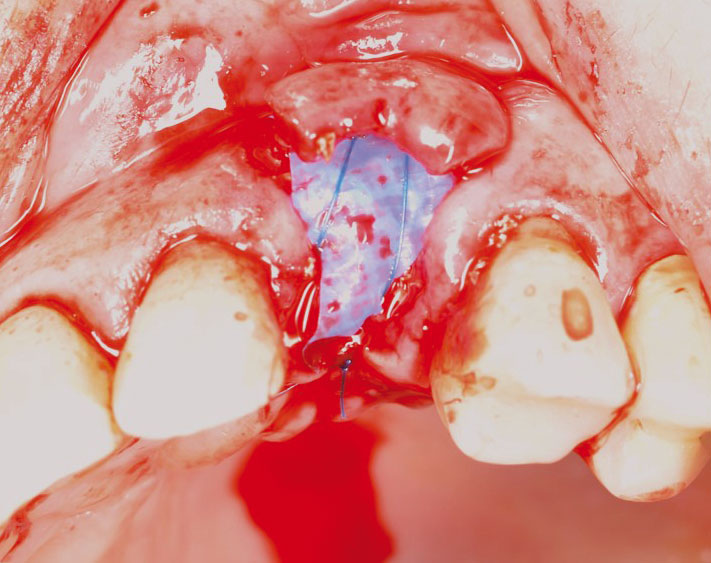

botiss cerabone® & Jason® membrane for GBR - Clinical case by Prof. Dr. Dr. D. Rothamel

Instable bridge situation with abscess formation at tooth #15 after apicoectomy